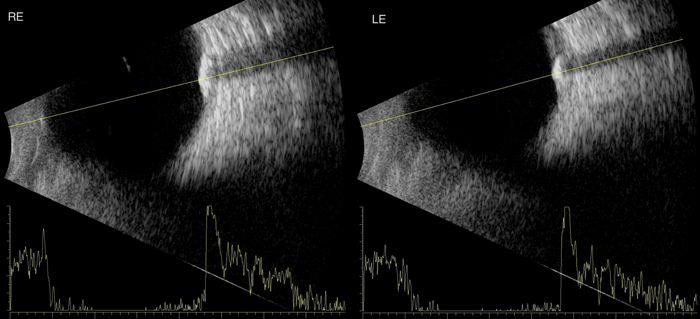

Figure 1.

An 83-year-old caucasian male was referred by his optometrist querying the cause of bilateral superotemporal fundal lesions. The patient was visually asymptomatic with an unremarkable past medical history. Clinically visual acuity was Right: 0.36 logMAR improving to 0.26 logMAR with pinhole and Left: 0.6 logMAR improving to 0.04 logMAR with pinhole. The anterior segment assessment showed moderate cortical lens opacity bilaterally and dilated fundoscopy revealed evidence of slight raised yellowish lesions (Figure 1) on the superior aspect of the superotemporal arcade bilaterally. B-scan ultrasound examination revealed highly reflective lesions and confirmed the clinical diagnosis of bilateral sclerochoroidal calcification (Figure 2).